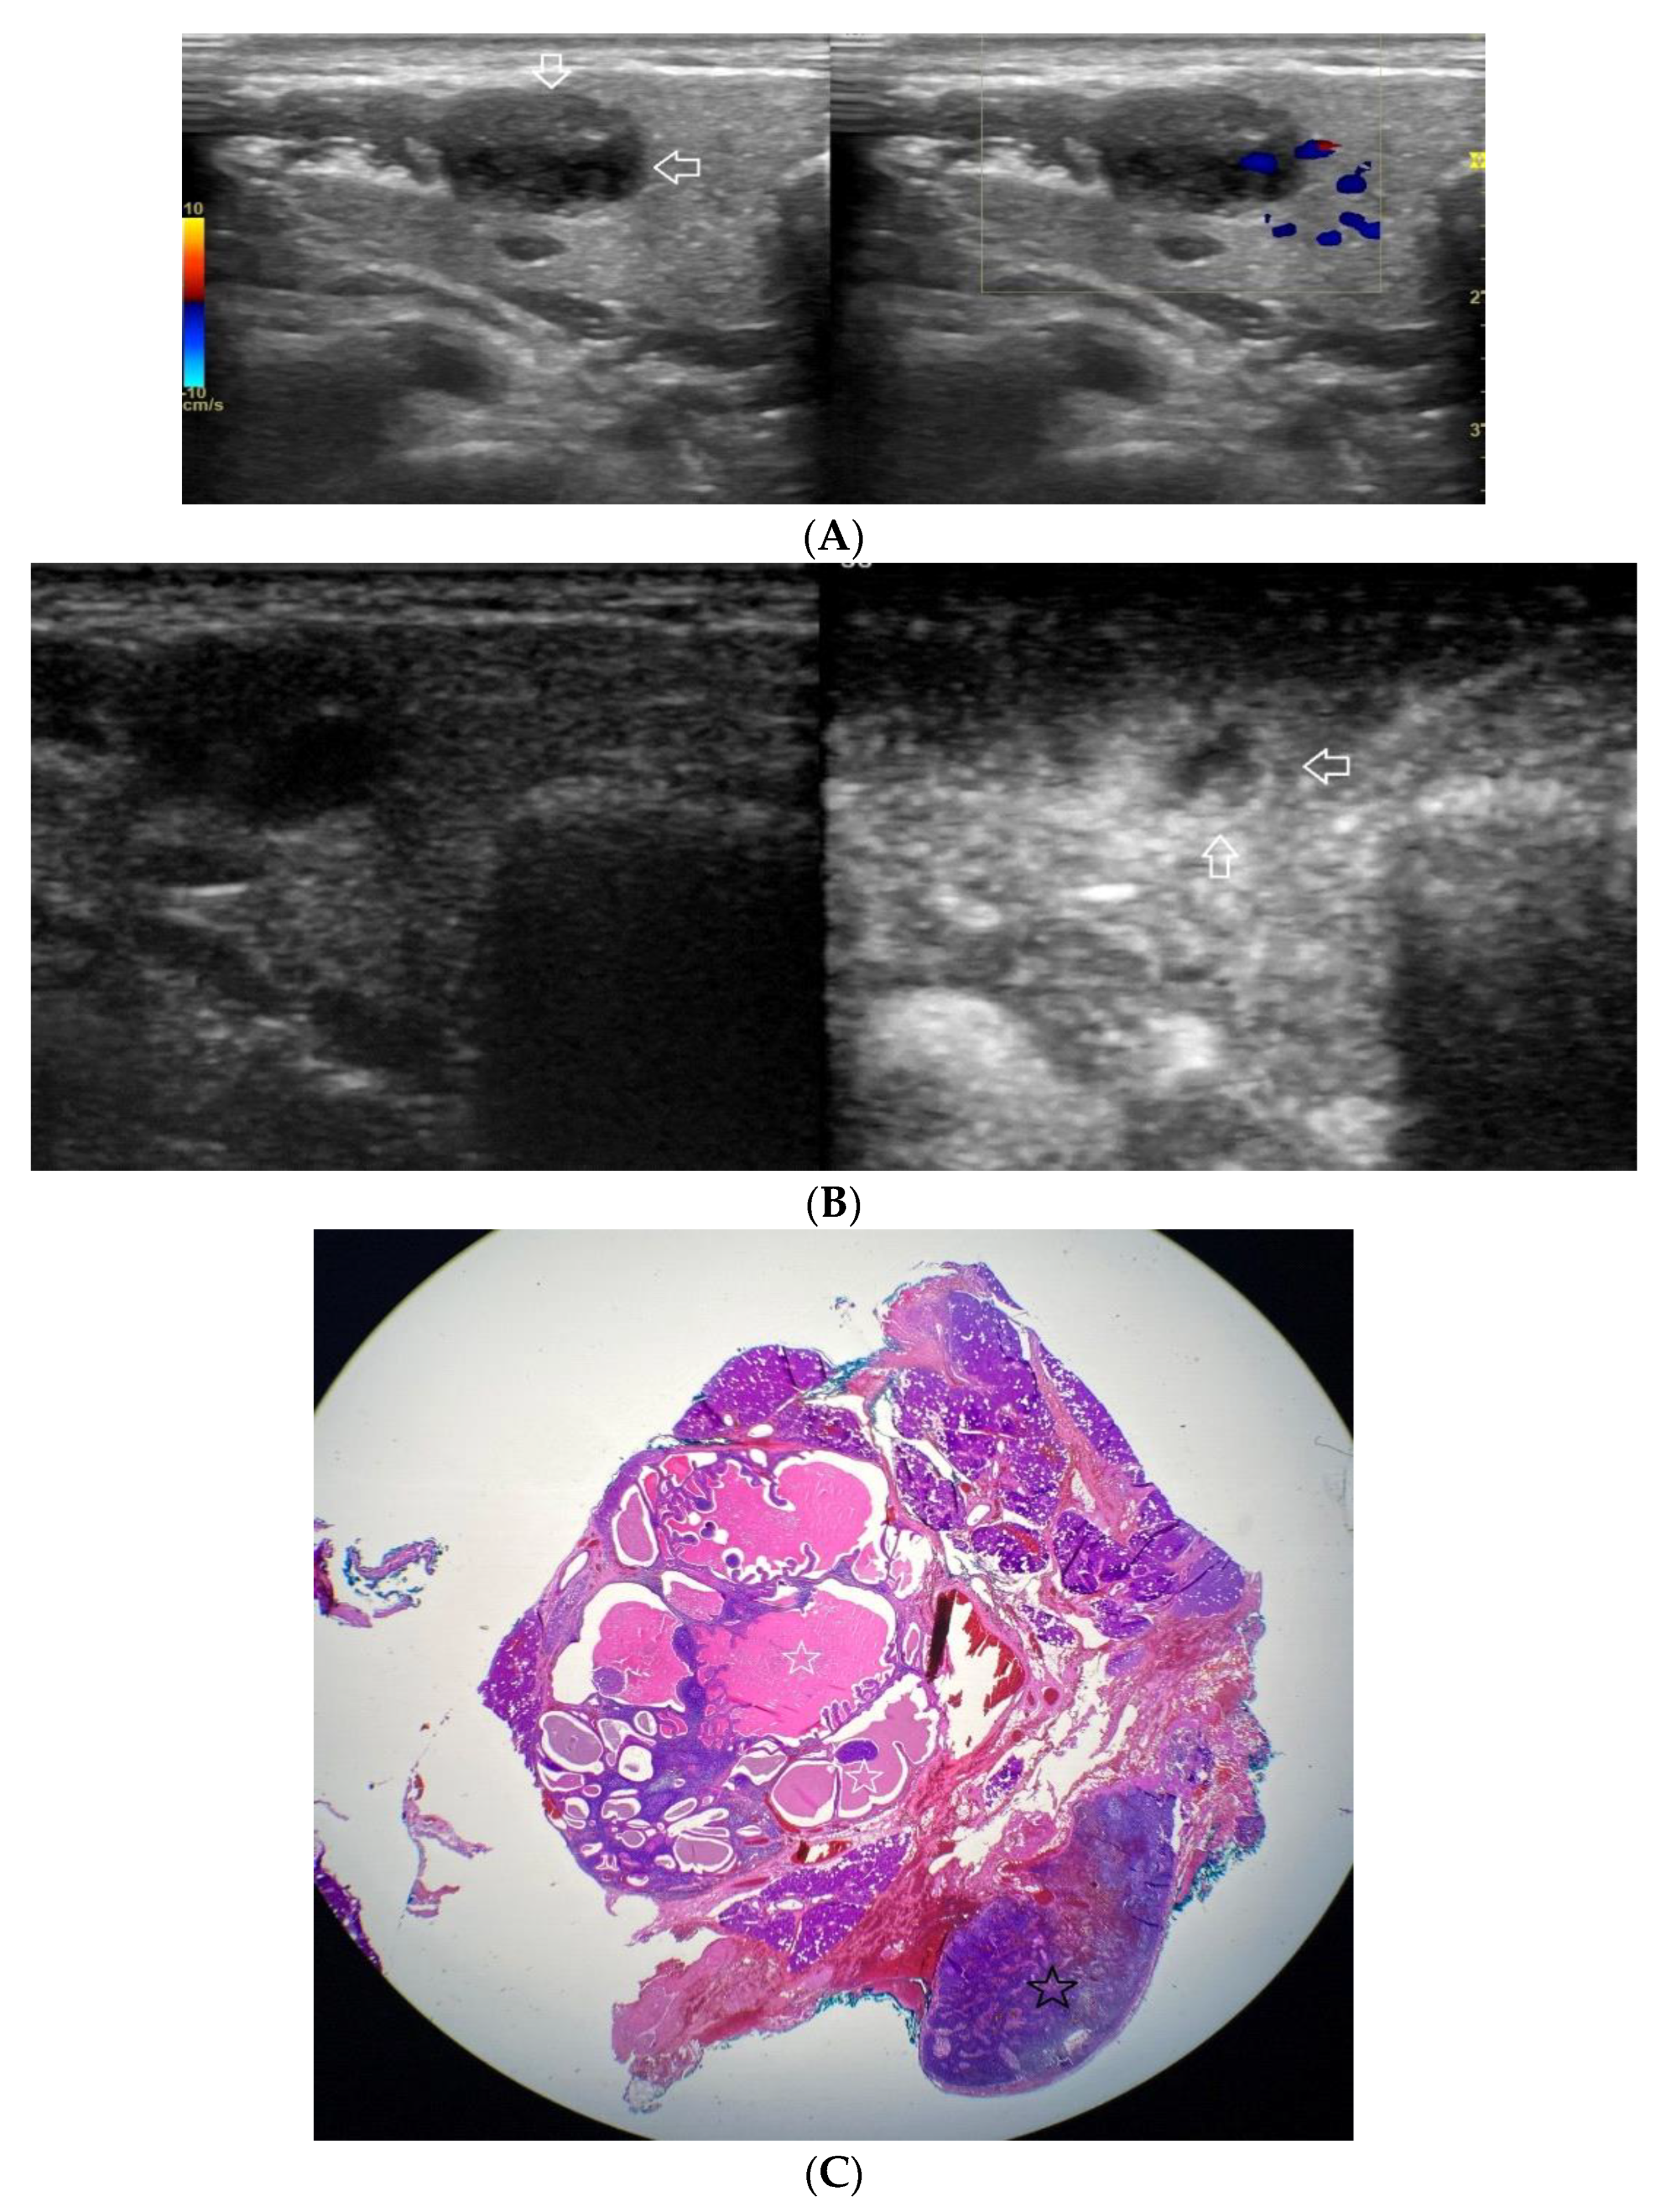

Figure 1.

(A−C) Lymphoepithelial carcinoma. (A) Routine ultrasonographic examination in B presentation and colour Doppler (CD): a hypoechogenic focal lesion of a heterogeneous echostructure (white arrows). On CD, low blood flow is observed. (B) Contrast-enhanced imaging in arterial phase: a strong heterogeneous enhancement of a lesion containing minor oval areas with no enhancement (white arrows). (C) Pathomorphological image, immunohistochemistry for CD3+. Aggregations of carcinomatous cells (white arrows) surrounded by scattered lymphoid tissue cells.

A correlation between professional photographs of CEUS imaging and those of microscope slides containing postoperative specimens was observed. It appears that the strong heterogeneous enhancement pattern is more likely to occur in benign lesions, while malignant, and malignant potential lesions tend to present weak heterogeneous enhancement. The foundation of such tendencies is revealed in pathomorphological specimens. Various tissues such as fluid and cartilage commonly present in salivary gland tumours, are generally poorly enhanced. The enhancement of such areas in CEUS is poor if any. The cross-section of Warthin tumour, for example, is presented by one or more often numerous minor cysts containing mucus.

Those not-enhanced areas and structures revealed on histopathological photographs overlapped (Figure 1, Figure 2, Figure 3, Figure 4, Figure 5 and Figure 6).